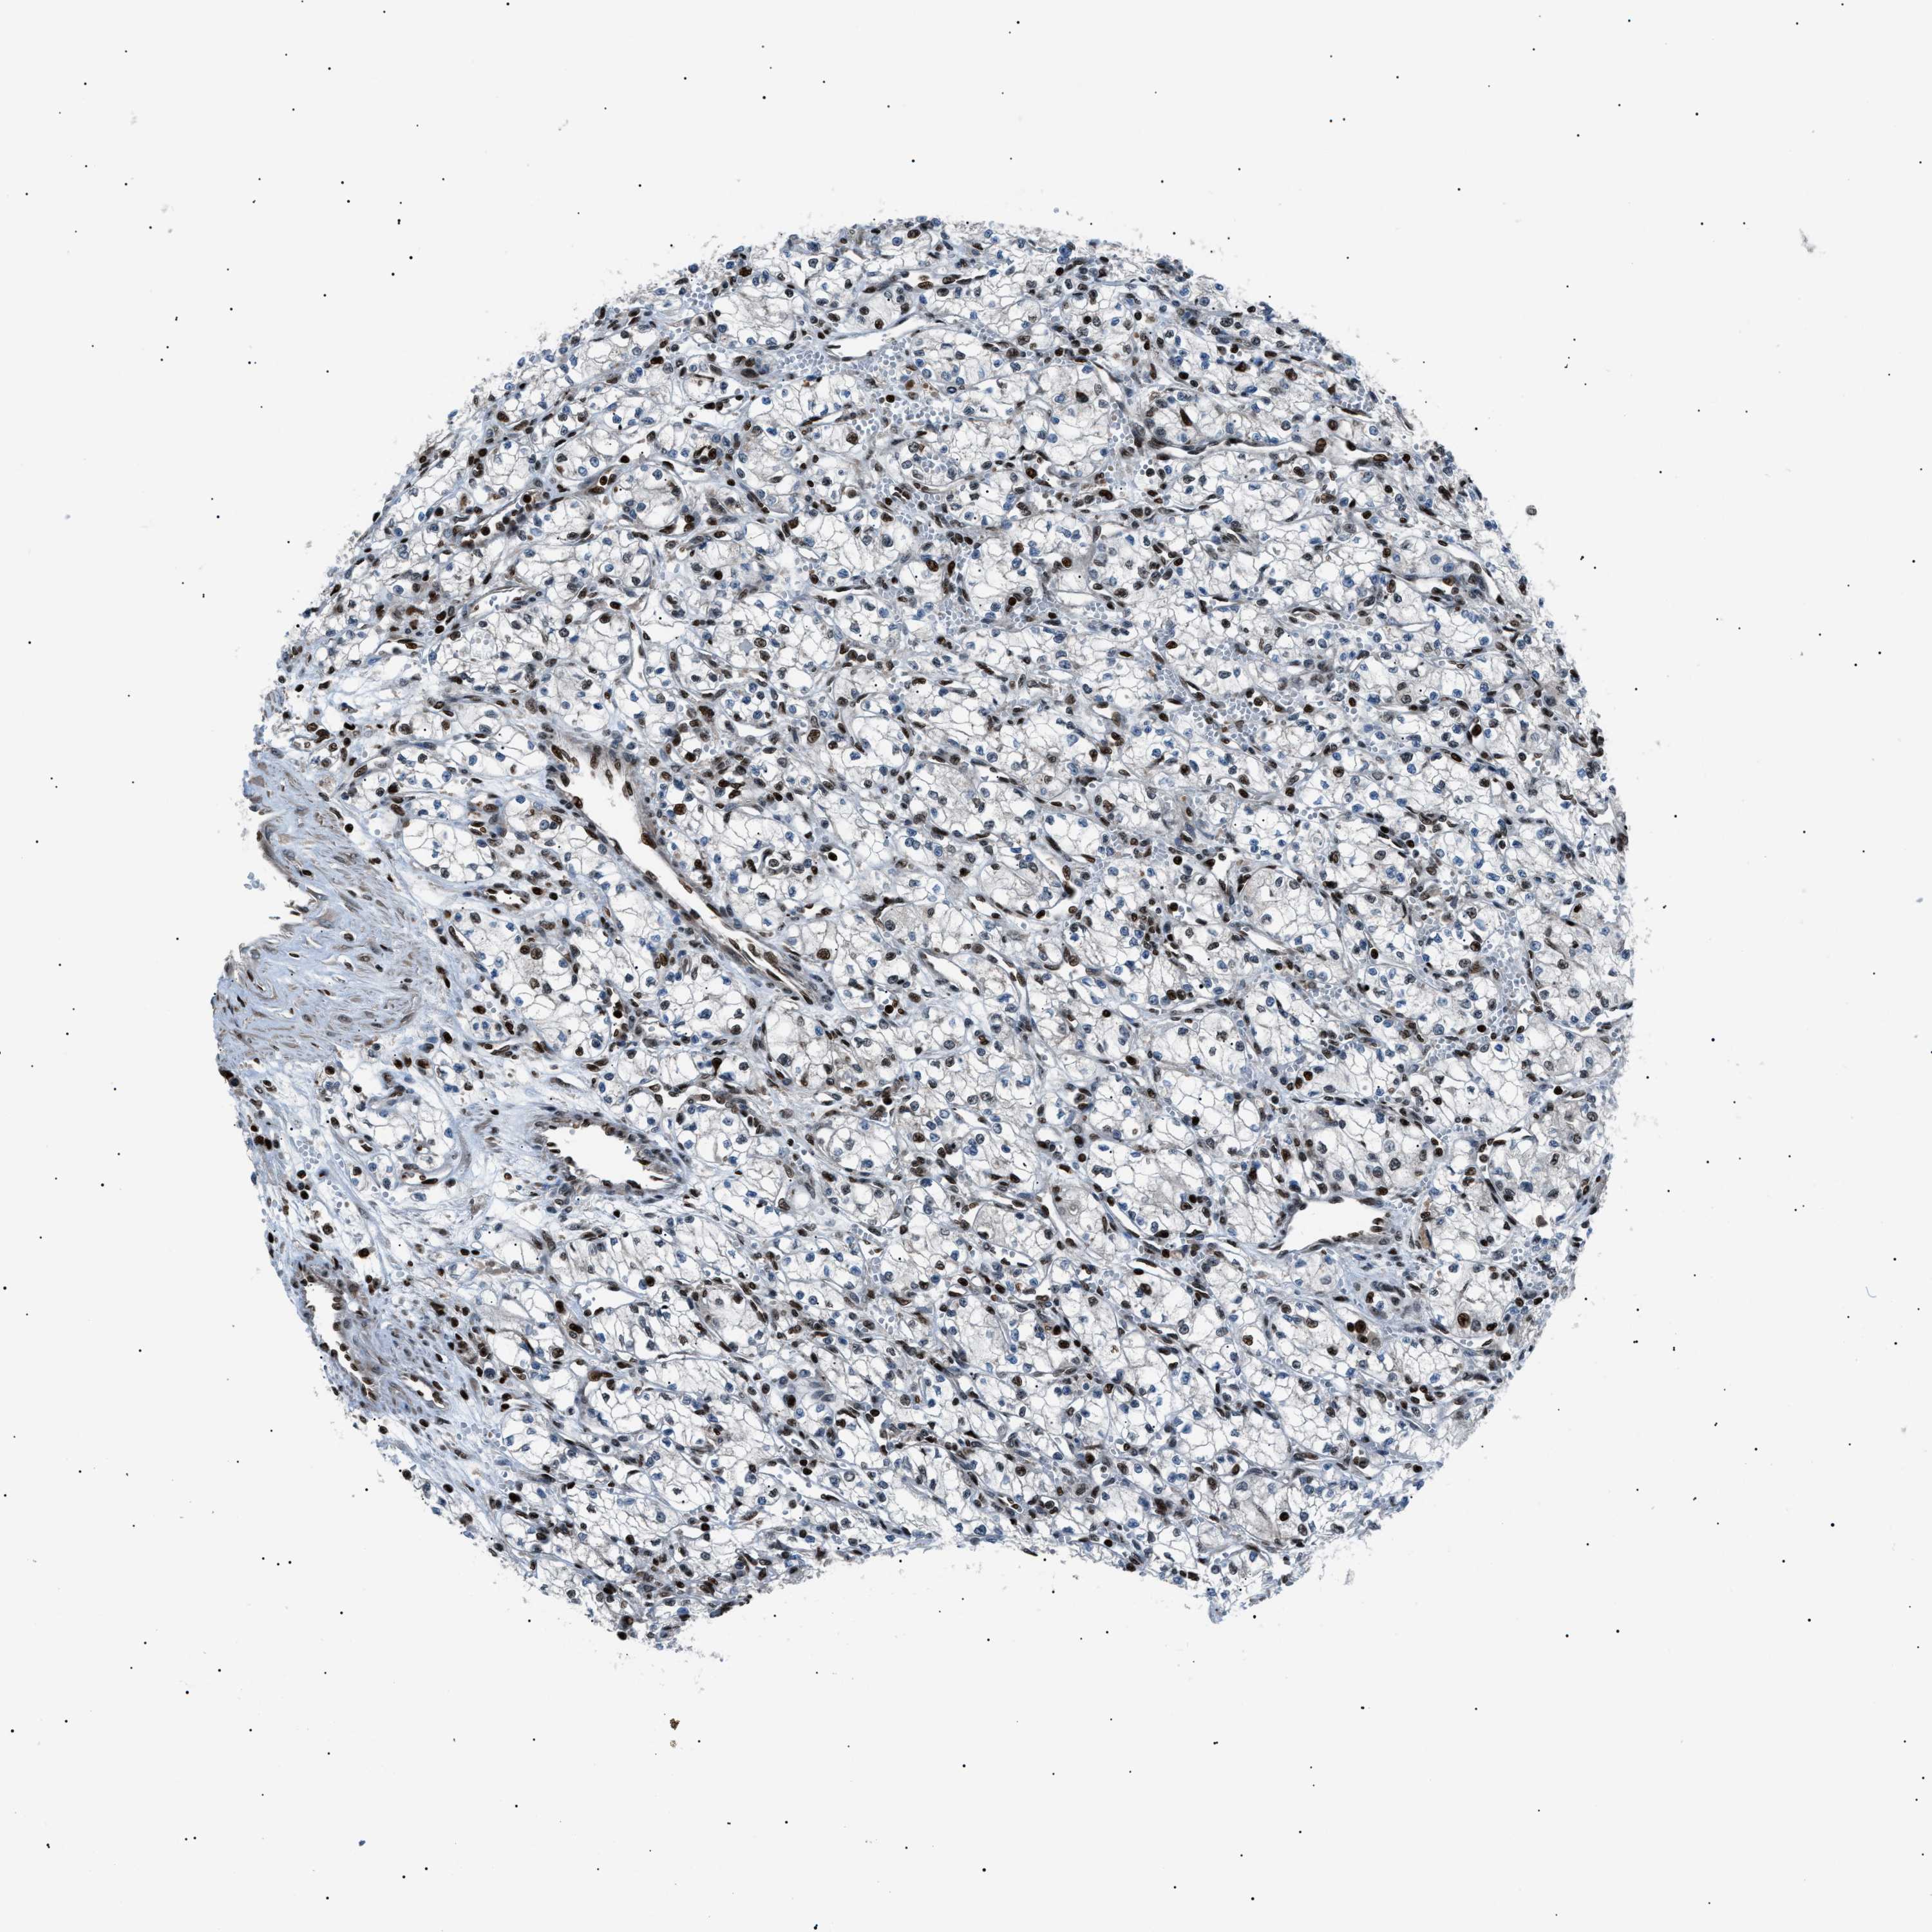

Renal cancer

Kidney chromophobe

KIDNEY CHROMOPHOBE (TCGA) - Interactive survival scatter ploti

The Survival Scatter plot shows the clinical status (i.e. dead or alive) for all individuals in the patient cohort, based on the same data that underlies the corresponding Kaplan-Meier plots. Patients that are alive at last time for follow-up are shown in blue and patients who have died during the study are shown in red.

The x-axis shows the expression levels (FPKM) of the investigated gene in the tumor tissue at the time of diagnosis. The y-axis shows the follow-up time after diagnosis (years). Both axes are complimented with kernel density curves demonstrating the data density over the axes. The top density plot shows the expression levels (FPKM) distribution among dead (red) and alive patients (blue). The right density plot shows the data density of the survived years of dead patients with high and low expression levels respectively, stratified using the cutoff indicated by the vertical dashed line through the Survival Scatter plot. This cutoff is automatically defined based on the FPKM cutoff that minimizes the p-score. The cutoff can be changed by dragging the vertical line or by entering a cutoff value in the square labeled "Current cut-off".

Under the Survival Scatter plot the p-score landscape (black curve; left axis) is shown together with dead median separation (red curve; right axis). Dead median separation is the difference in median mRNA expression between patients who have died with high and low expression, respectively. It is calculated as follows: median FPKM expression of dead patients with high expression - median FPKM expression of dead patients with low expression. This is intended to aid the user in visually exploring custom cutoffs and the associated p-scores and dead median separation.

Individual patient data is displayed and can be filtered by clicking on one or more of the category buttons on the top of the page. Categories describing expression level and patient information include: high, low, alive, dead, female, male and tumor stages. The scale of the x-axis can be toggled between linear and log-scale by clicking on the "x log" button. Mouse-over function shows TCGA ID, patient information and mRNA expression (FPKM) for each patient.

& Survival analysisi

Kaplan-Meier plots summarize results from analysis of correlation between mRNA expression level and patient survival. Patients were divided based on level of expression into one of the two groups "low" (under cut off) or "high" (over cut off). X-axis shows time for survival (years) and y-axis shows the probability of survival, where 1.0 corresponds to 100 percent.

PRKX is not prognostic in Kidney Chromophobe (TCGA)